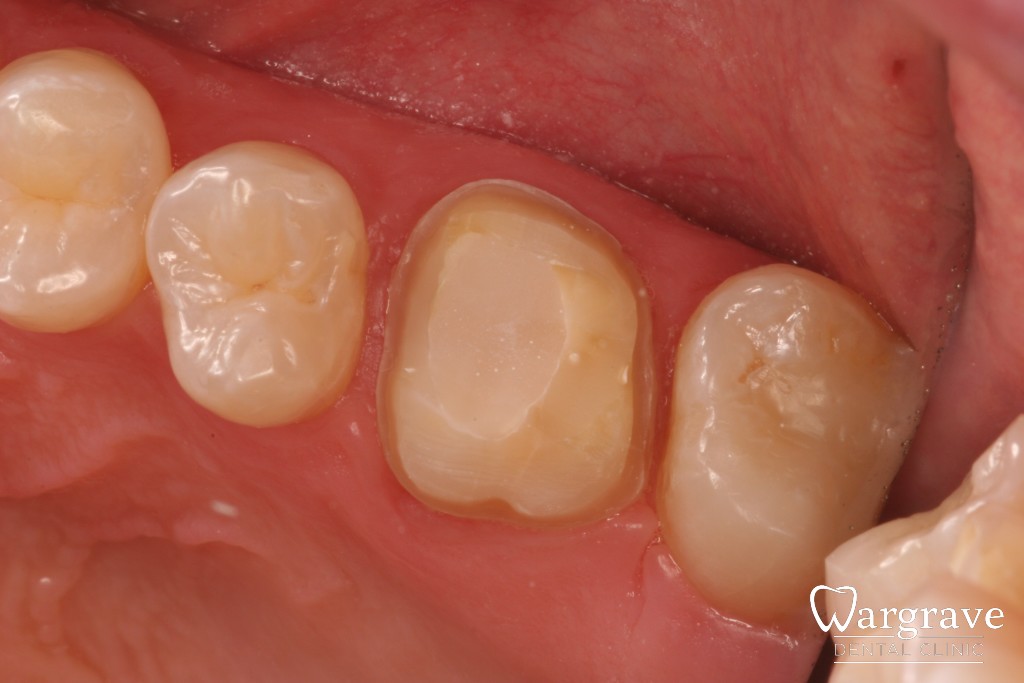

Porcelain Bonded crowns (posterior)

When back teeth break, provided there is sufficient natural tooth remaining, they can be restored with a porcelain crown. This crown has an underlying metal substructure making it very durable.